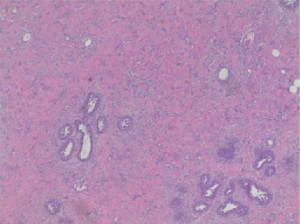

PASH is diagnosed pathologically by visualization of myofibroblasts arranged in slit-like spaces with intervening collagen (5). On ultrasound, PASH appears as a hypoechoic, circumscribed mass, similar to a fibroadenoma (6). On mammography it appears as a noncalcified, circumscribed mass, also similar to a fibroadenoma (6). On physical exam, most cases of PASH present with a palpable firm mass; rarely does it present as a diffuse, infiltrative process resulting in bilateral breast hypertrophy (7) such as our case. Observation or surgical excision is the recommended treatment (8). We present a case of bilateral PASH in a 12-year-old female and our surgical treatment in accordance with the CARE reporting checklist (available at https://abs.amegroups.com/article/view/10.21037/abs-25-46/rc).

In the operating room, an inframammary incision was made, and flaps were elevated, similar in technique to starting a nipple sparing mastectomy (Figure 2). The dissection plane was difficult to discern because the pathology was diffusely infiltrated into the breast tissue. There was no discrete mass with clear borders. After excision, the only remaining breast tissue was <1 cm thickness directly under the nipple areolar complex (NAC) (Figures 2,3). This was spared in an effort to allow for future natural breast development and to maintain blood supply to the nipple. Final surgical pathology resulted as PASH, usual ductal hyperplasia, and focal apocrine metaplasia (Figure 4).

Two months later, the patient returned to the clinic with expansive growth of the left breast, similar in appearance and timeline to the right breast (Figure 5). An ultrasound was obtained that showed a large mass encompassing all four quadrants with homogeneous echotexture and scattered cystic spaces. Given a similar presentation to the other breast, a CNB was again performed. Using a 12-gauge BARD core device under direct ultrasound visualization, 5 samples were obtained. This resulted as a juvenile fibroadenoma, which was concordant with imaging. The patient again underwent left breast excisional biopsy (Figure 6). The incision, dissection, and closure were nearly identical to her contralateral surgery. Final pathology resulted as juvenile fibroadenoma, PASH, and fibrocystic changes (Figure 7) as confirmed by two pathologists.

PASH can be seen histologically with other benign breast diagnoses, such as our patient, but could also be misdiagnosed as malignant, specifically angiosarcoma. In PASH, the visualized slit-like spaces are made up of myofibroblasts with collagen between the slits whereas in angiosarcoma, the slit-like spaces are anastomosing blood vessels (5). Immunohistochemistry (IHC) can be used to confirm PASH from angiosarcoma. PASH tumors express CD34, vimentin, and focally smooth muscle markers such as actin, desmin and bcl-2 (11). This is in contrast with angiosarcoma where endothelial markers such as CD31 and factor VIII are positive (11). IHC was not done for our patient because after discussion with staff pathologists who read our patient’s surgical pathology, none felt that IHC was necessary. Her clinical course and history were more consistent with PASH than angiosarcoma. However, in cases where there is confusion, such as a patient with a history of radiation that would raise the risk of an angiosarcoma, use of IHC could help differentiate the diagnosis.